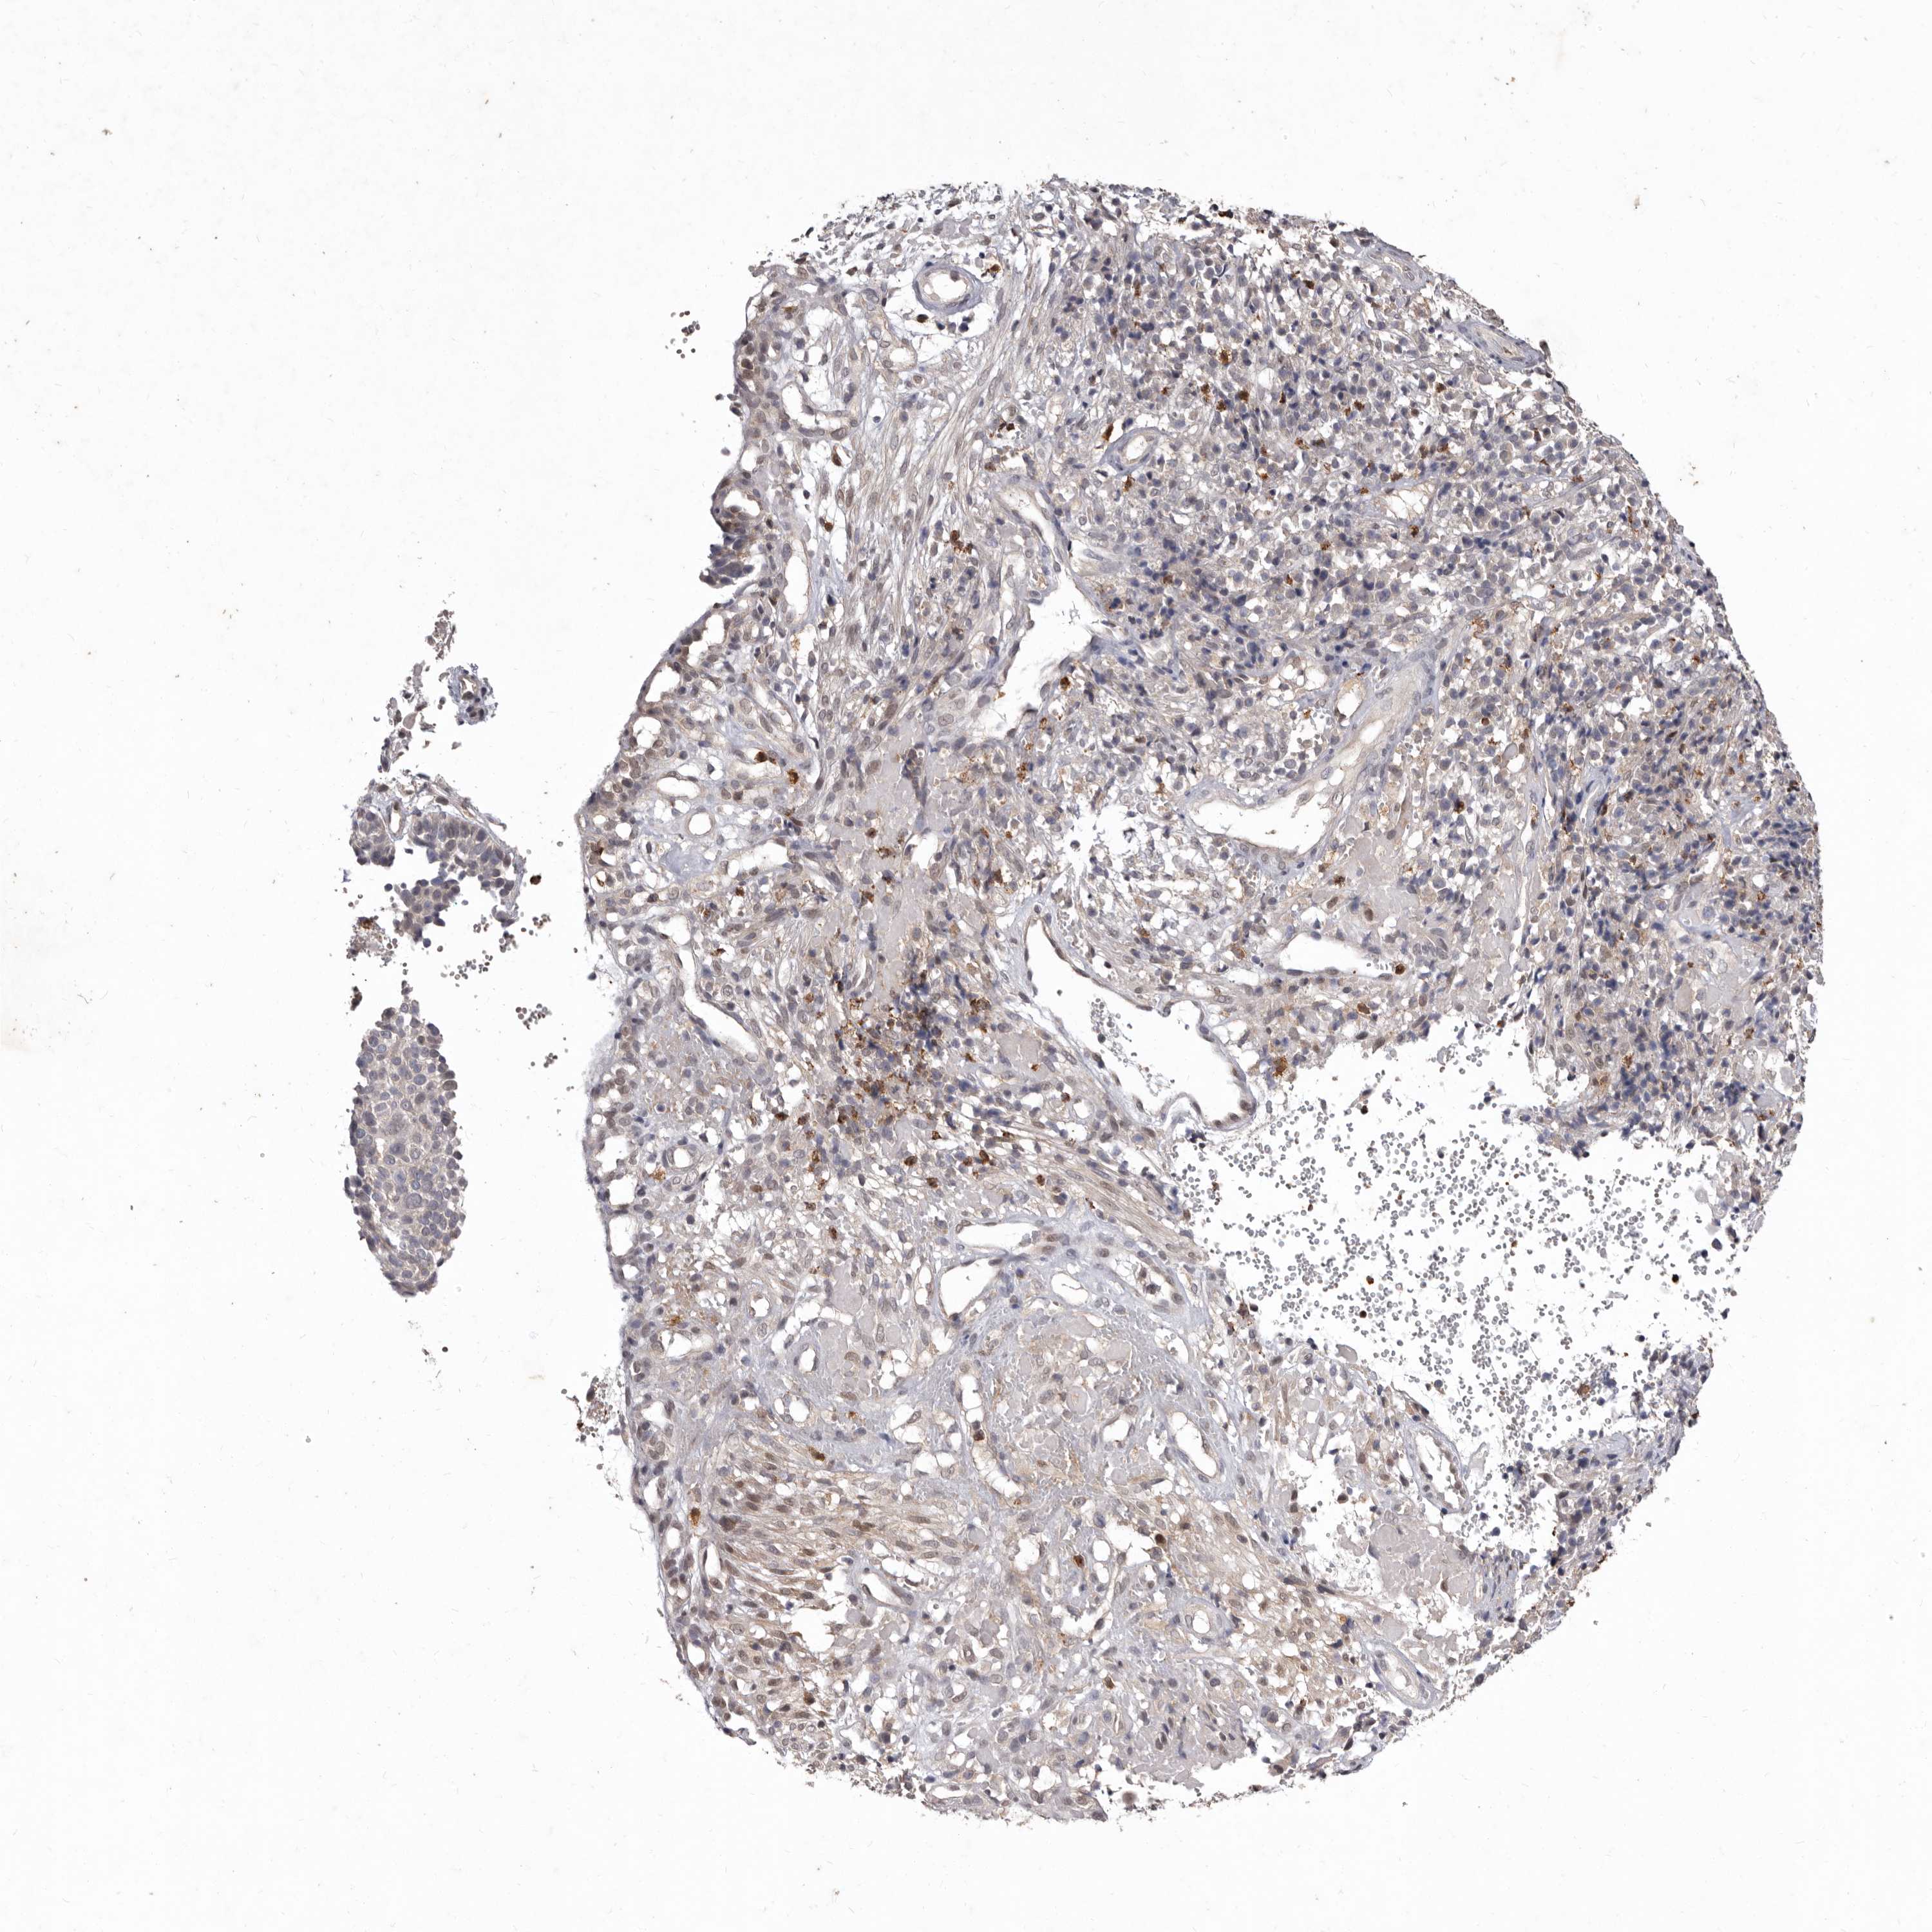

CERVICAL CANCER - Protein expressioni

A mouse-over function shows sample information and annotation data. Click on an image to view it in a full screen mode. Samples can be filtered based on level of antibody staining by selecting one or several of the following categories: high, medium, low and not detected. The assay and annotation is described here.

Note that samples used for immunohistochemistry by the Human Protein Atlas do not correspond to samples in the TCGA dataset.

Antibody stainingi

Antibody staining in the annotated cell types in the current human tissue is reported as not detected, low, medium, or high, based on conventional immunohistochemistry profiling in selected tissues. This score is based on the combination of the staining intensity and fraction of stained cells.

Each image is clickable and will lead to virtual microscopy that enables deeper exploration of all samples and also displays staining intensity scores, fraction scores and subcellular localization as well as patient and tissue information for each sample.

HPA022434

HPA022953

HPA022959

HPA028758

CAB007783

Staining

High

Medium

Low

Not detected

Intensity

Strong

Moderate

Weak

Negative

Quantity

>75%

75%-25%

<25%

None

Location

Nuclear

Cytoplasmic/membranous

Cytoplasmic/membranous,nuclear

Squamous cell carcinoma, NOS

Adenocarcinoma, NOS